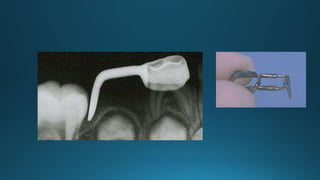

Distal shoe space maintainer:

DESIGN OF WIRE LOOP

INDICATION:

CONTRAINDICATION: